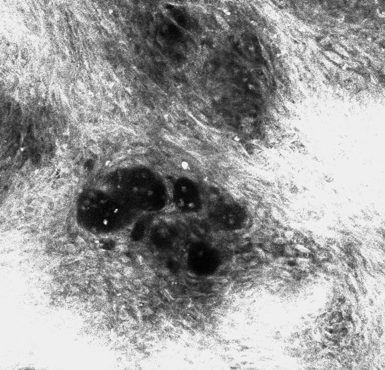

This technology is called Reflectance Confocal Microscopy (RCM). It is a laser that in low frequency, transforms energy into images. The images are black and white and show details at cellular level, in other words, it is a life biopsy. We can observe the surface of the skin (epidermis and papillary dermis) and its architecture, dinamically. Moreover, this image system allows us to see the skin horizontally at multiple levels, creating a stack of images that can be transformed in a 3D model. And all this is happening with no pain and no side effects.

So far, our research team is working to correlate the RCM features to histopathology findings. The next step will be to use the RCM as a guide to perform biopsies more precisely. One previous study showed that when the RCM detects a vesicle-like structures (called Pautrier microabscess), it increases the accuracy of the biopsy.